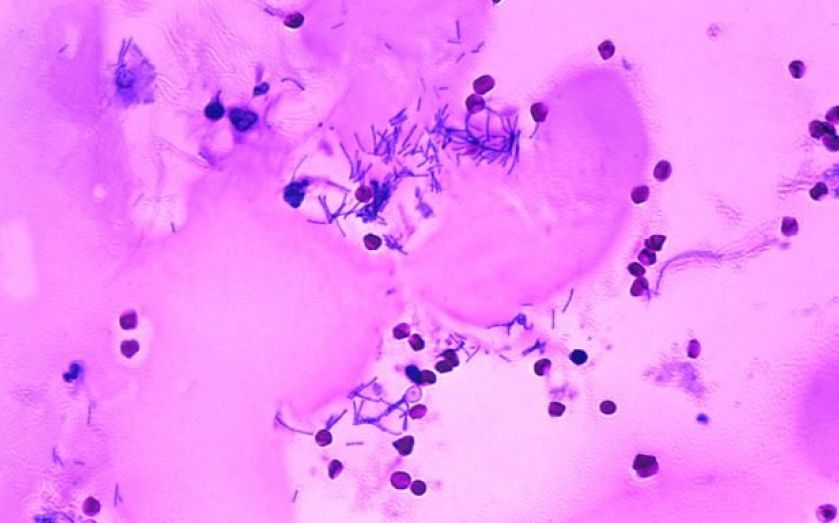

How to cure anthrax. Inhalation anthrax can also be treated with a combination of antibiotics and injections of raxibacumab or obiltoxaximab (monoclonal antibodies that bind anthrax toxins in the. [4] anthrax vaccination is recommended for people at high risk of infection. Inhalational anthrax results from breathing anthrax spores into the lungs.

Types of anthrax the types of anthrax reflect the different ways the bacteria enter your body. Natural ways to cure anthrax white fir. There are other treatments, including a vaccine.

Introduction anthrax is an ancient zoonotic disease which primarily infects herbivores with humans occasionally being infected. Cutaneous anthrax is easy to cure if it is treated early with appropriate antibiotics. It is excellent for use in case.

Antibiotics work in two main ways, by killing the anthrax or by stopping the anthrax from growing. For people who have been exposed to anthrax (but have no symptoms of the disease), providers may prescribe preventive.